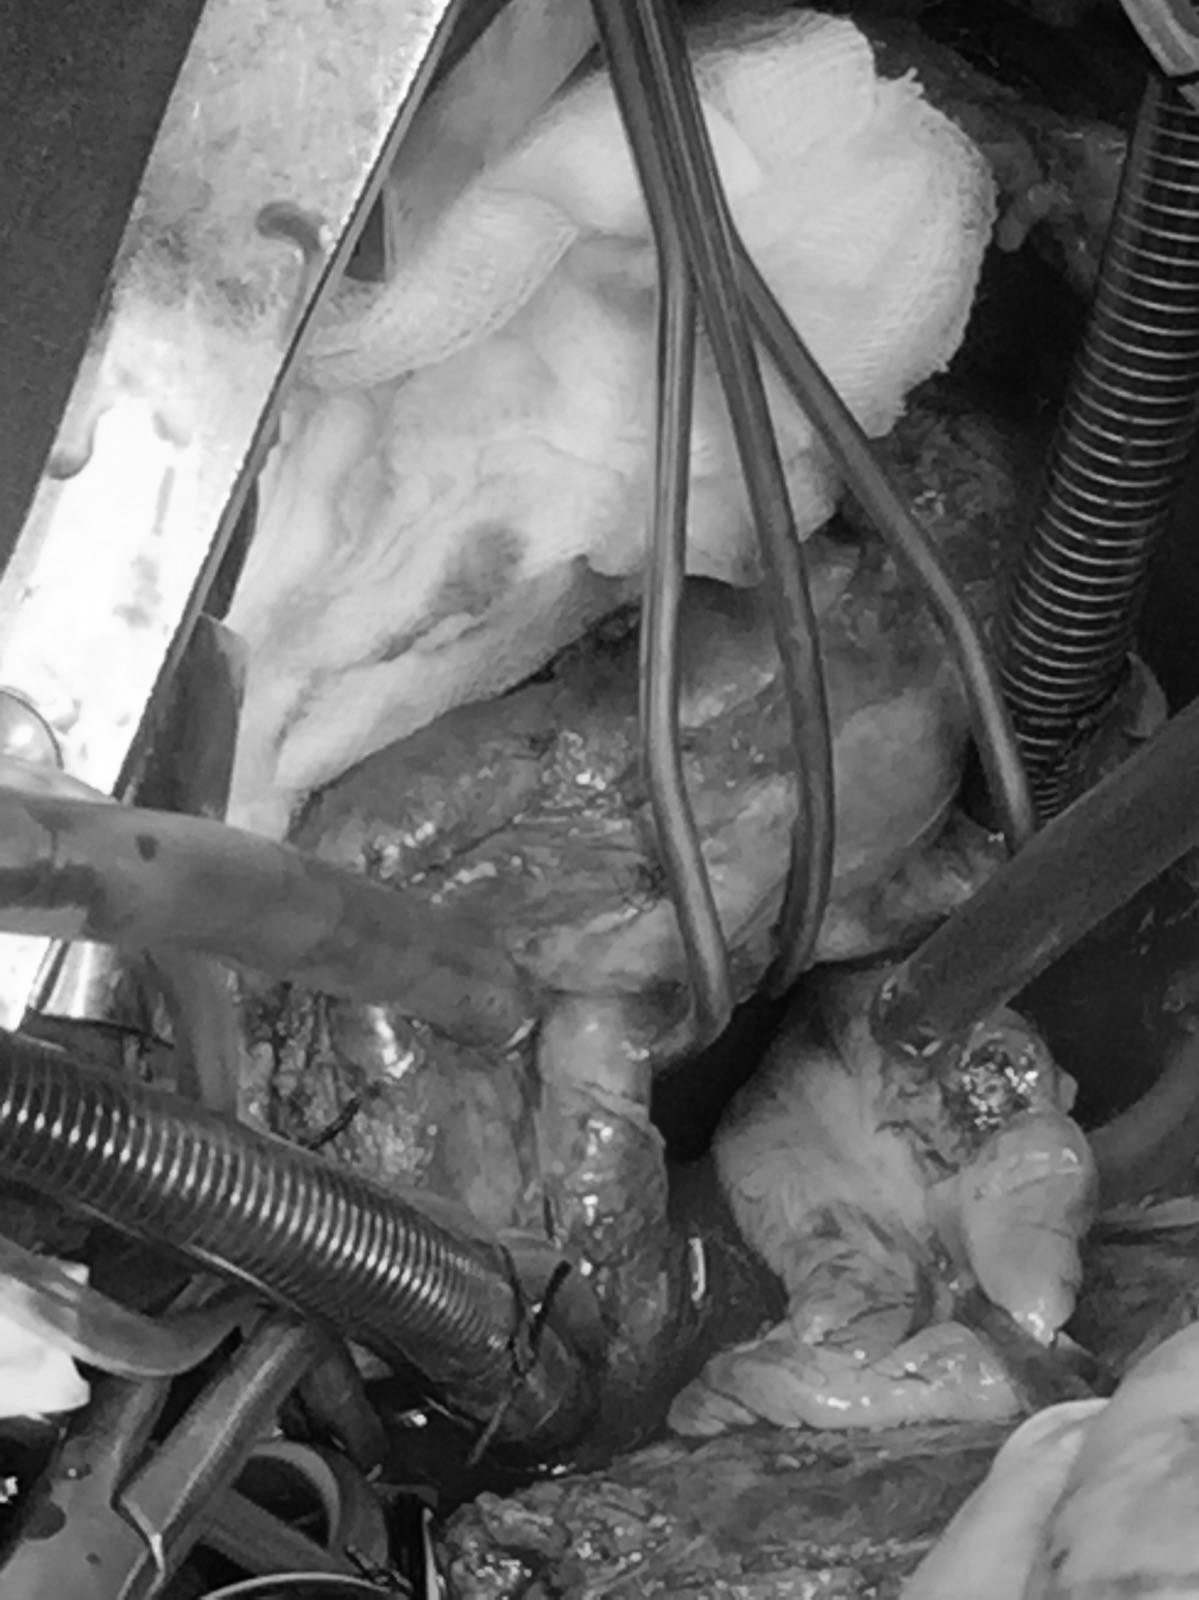

Ventriculoperitoneal shunt is the most common and most effective therapeutic modality for the management of hydrocephalus. While most frequent complication is shunt dysfunction, abdominal complications may also occur at a rate of 25%, where 0.01-0.07% consists of colonic perforation. Despite being rare, a delayed diagnosis and treatment has a relatively mortal course. Once the diagnosis is established, prompt treatment should be initiated with accompanying removal of the catheter. In this case report, we presented a patient who had a ventriculoperitoneal shunt catheter protruding from anus with diagnostic and therapeutic approach in the guidance of the literature.